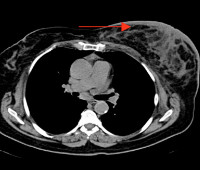

Компьютерная томография (КТ) молочных желез. Метод компьютерной рентгенодиагностики, позволяющий сканировать ткани молочной железы послойно. В компьютерной томографии пациент лежит в цилиндрической камере с источником рентгеновского излучения и датчиком в горизонтальной плоскости. Изображение каждого среза передается на компьютер, где оно обрабатывается и объединяется с другими данными. КТ молочных желез дополняет обзорную маммографию и служит для выяснения распространенности и функциональности опухолевого процесса, интереса лимфатических узлов, прорастания опухоли в стенку грудной клетки.

КТ молочных желез дает наиболее точную клиническую информацию о состоянии здоровья пациента. Поэтому это имеет особое значение в диагностике патологии молочной железы. Процедура в основном назначается врачами и онкологами в случае подозрения на рак молочной железы. Тест обычно не используется в профилактических целях. По сравнению с ультразвуком и маммографией компьютерная томография более информативна. С его помощью вы можете визуализировать не только мягкие ткани, но и нижележащие структуры (мышцы, хрящи, кости). Также во время обследования диагност обращает внимание на состояние лимфатических узлов с целью выявления метастазов. Кроме того, дополнительные манипуляции могут проводиться под контролем специалиста по КТ, в частности, для изъятия материала для биопсии после обнаружения новообразований.